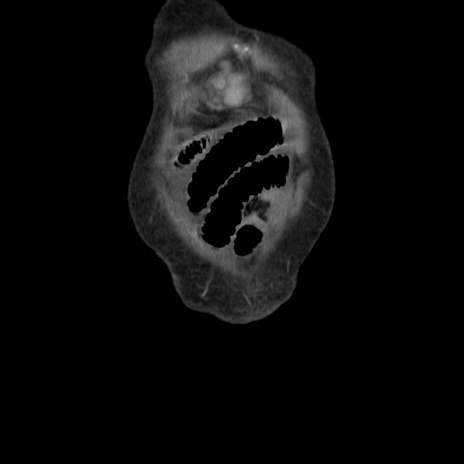

横断像